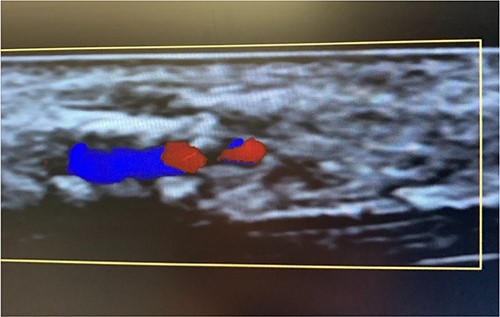

An 87-year-old male presented after a syncopal fall with a subdural hematoma who underwent emergent evacuation. Postoperatively he was admitted to the intensive care unit with a 4F × 10 cm Mini Stick MAX (Fig. 1) radial arterial line that was sutured in place. On postoperative day one, he became confused and self-discontinued the arterial line. Upon examination, it was noted that a portion of the catheter had twisted upon itself and the removed catheter was not completely intact (Fig. 2), indicating the possibility of a retained foreign body. A bedside ultrasound was used to identify and confirm the catheter still within the artery (Figs 3 and 4) and vascular surgery was consulted. The patient was brought to the operating room for a right radial artery exploration and removal of catheter under general anesthesia (Fig. 5). The patient recovered uneventfully with intact distal radial blood flow.

Color flow doppler distinguishing between arterial versus venous flow.